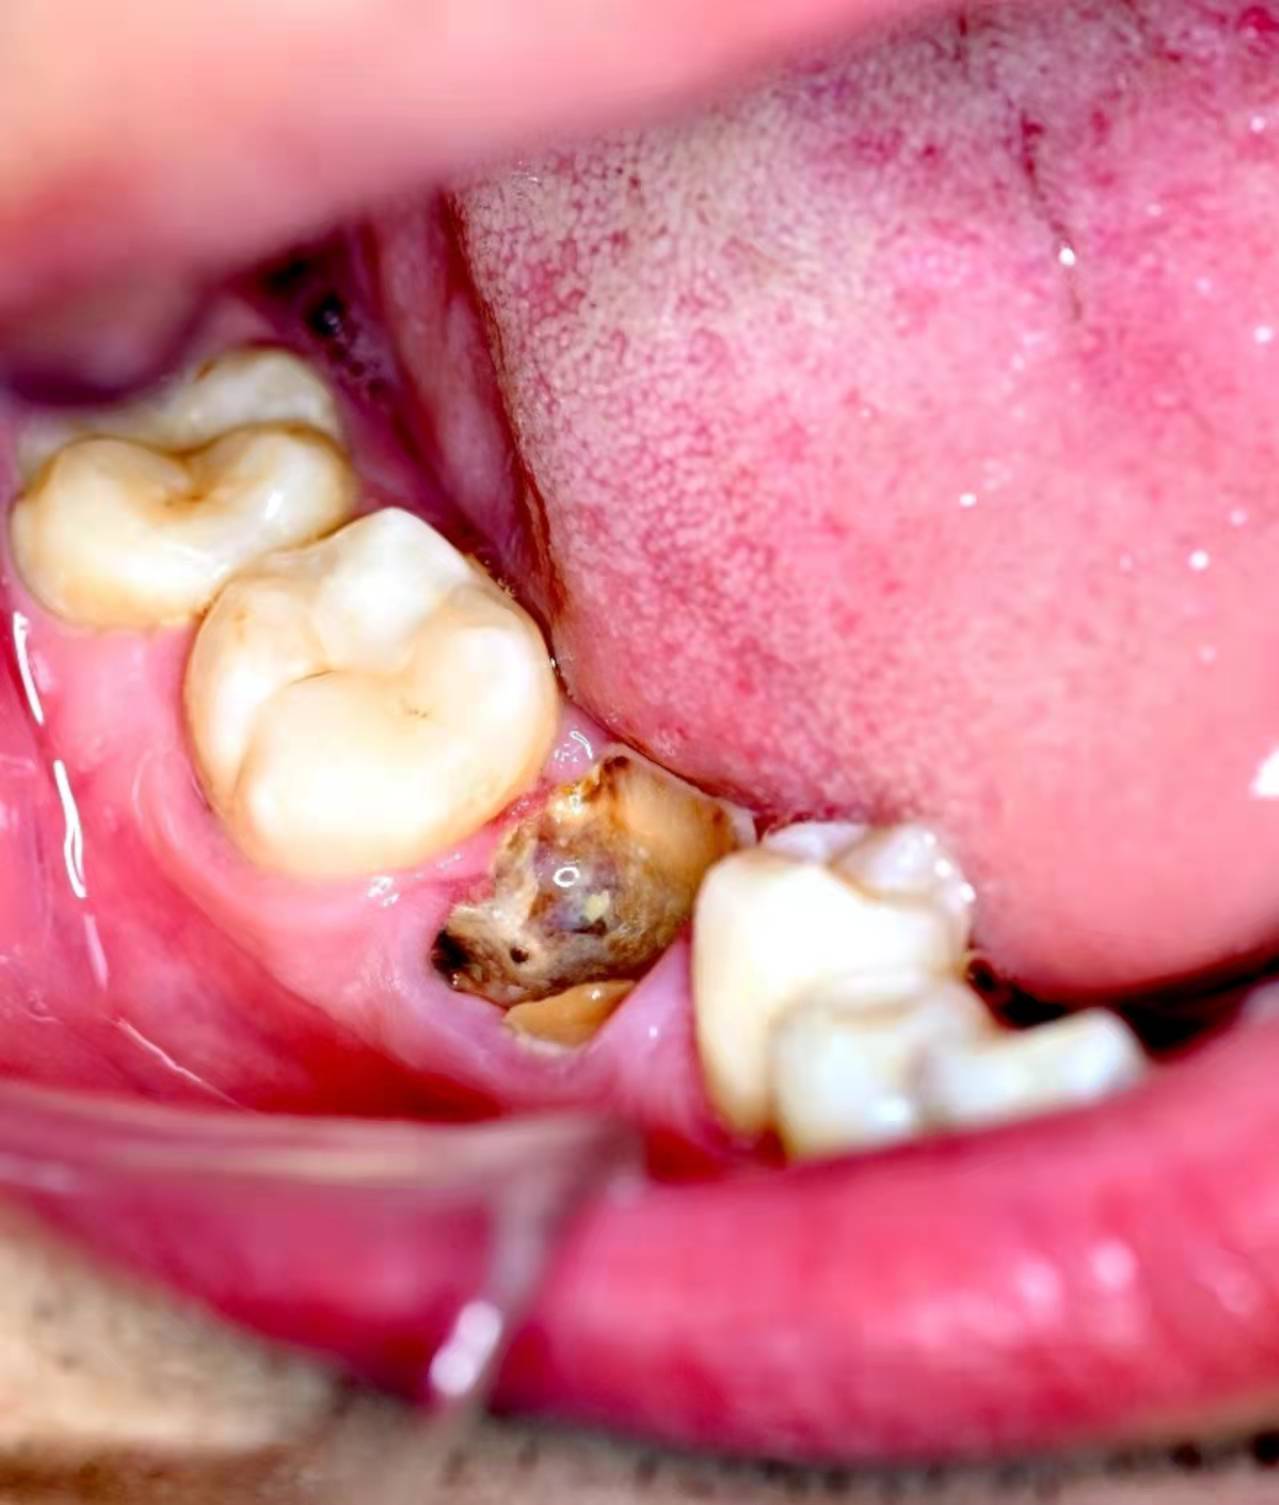

口內(nèi)照:

拔下來的殘根,全部拿出: